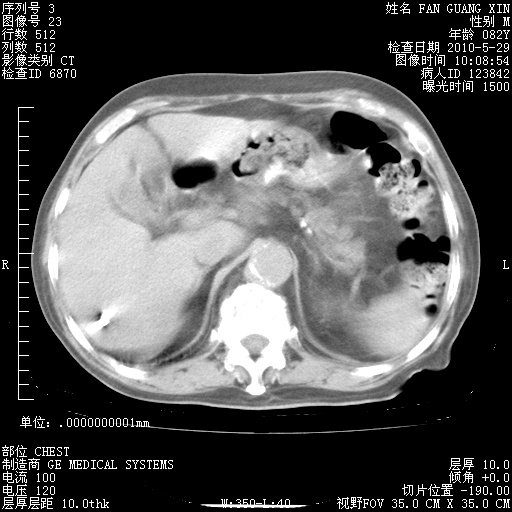

再治疗10天后的肺部CT

再治疗10天后的肺部CT 纵膈窗

从白细胞总数和中性比例看好像合并感染。肺部纹理好像比上次多,支气管炎?其他感染?

阅读此次胸部CT,肺间质渗出性改变较入院时有吸收。目前从体温、白细胞、中性分叶明显增高,肯定存在细菌感染(发生医院感染哦,若无消化道及泌尿系统等感染的依据,肺部感染可能大)。若你院头孢哌酮舒巴坦钠耐药率较高,同意你的方案,若48小时体温仍高,可考虑使用碳青霉稀类抗菌药物,同时可予超声雾化、注意滴数时加大液体量。白蛋白33.30g/L较低哦,需加强营养等支持治疗。